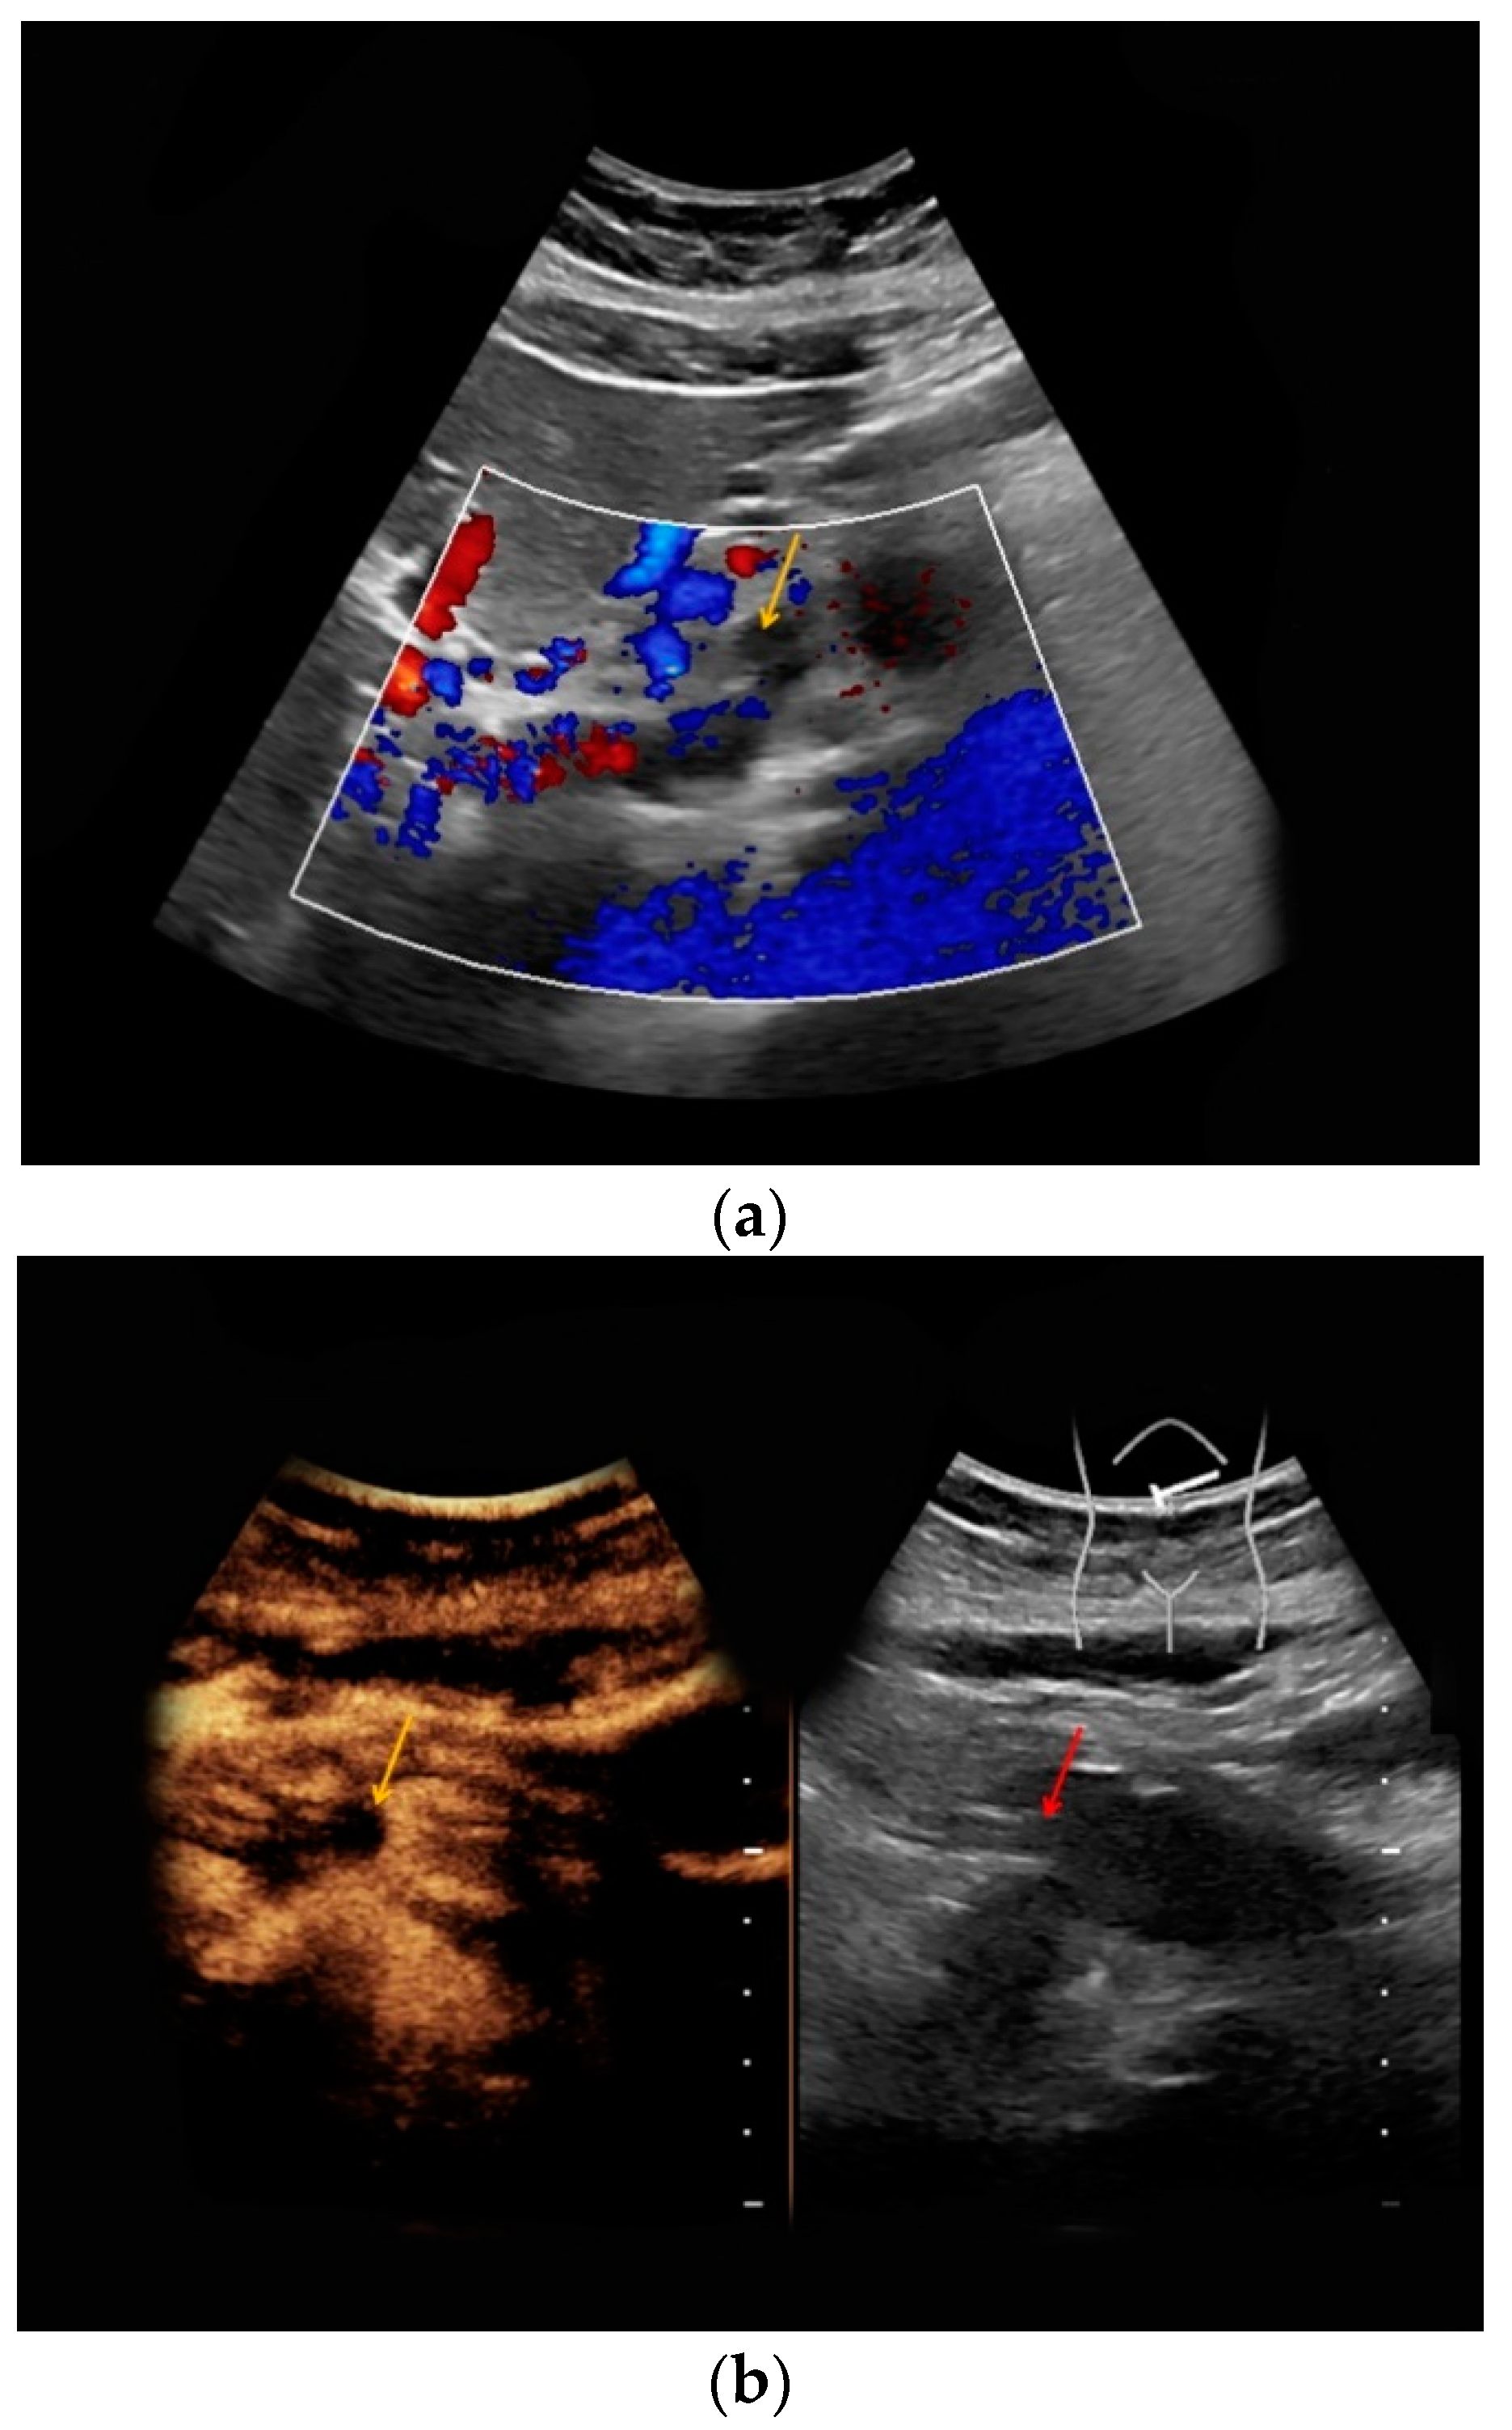

| #5 | 34 | 14 | Superior mesenteric vein thrombosis | B-mode: no abnormalities Doppler: no Doppler signal in the superior mesenteric vein CEUS: only slightly marginal microbubble distribution in the superior mesenteric vein | small superior mesenteric vein thrombosis |